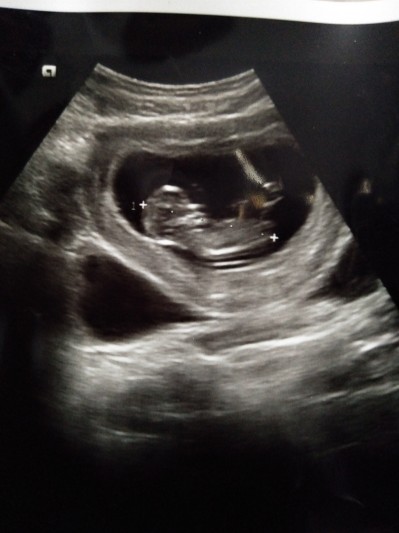

Hastaneye gittim doktor bana yüzde 70 bebeğimin kız olduğunu söyledi fakat fazla hareketli olduğundan tam belli olmuyor dedi bu durumdan bazı yakın çevreminde haberi var ve onlarda başının erkek çocuk olduğunu söylüyorlar bizde merak ediyoruz açıkçası 3 aylığa girdik nerdeyse sizinle de paylaşmak istedim tahminleriniz nelerdir?

Gebelik haftası 11-2

Kafası ve kese şekli erkek ama Allah hayırlısını versin

Kese ve bebek şeklimiz benziyor . 13 haftaligiz fetal DNA da kız olduğunu ogrendik yani kesin kromozom . Ultrasyonda anlamadı doktor bizimkide çok hareketli kalp atışını bile sabitleyemiyoruz bazen hep oynuyor :)